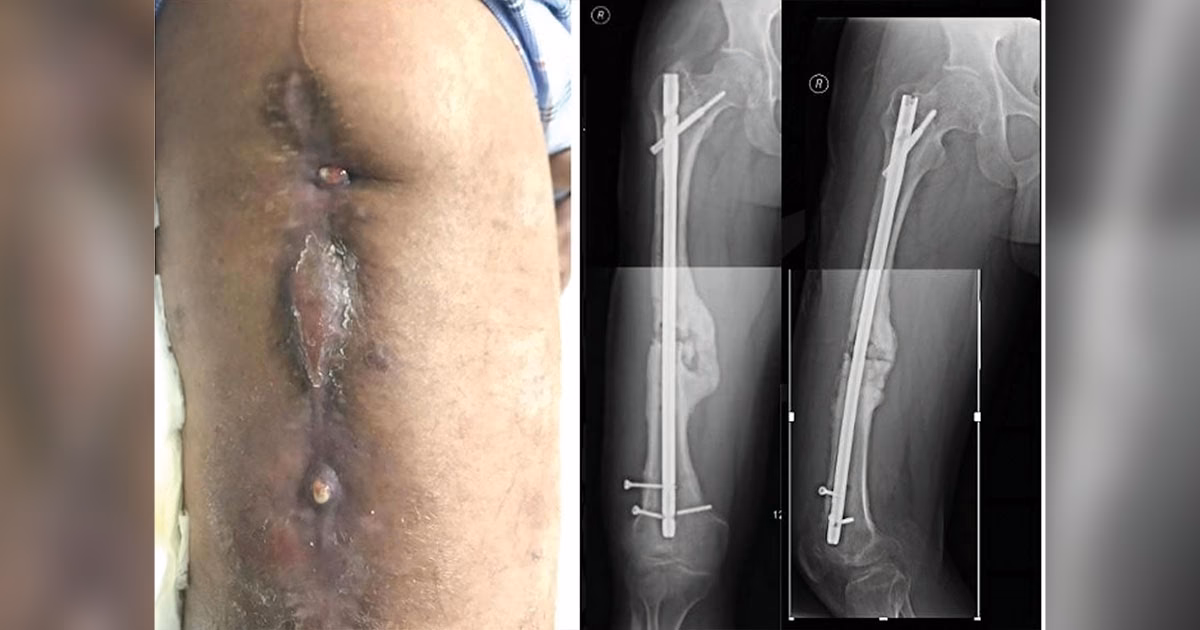

• Fistel eller sinusgang, der kommunikerer med knoglen eller implantatet.

• Lokale tegn på infektion som rødme, hævelse og varme.

• Vedvarende eller nyopstået væsken fra såret.

• Tidlig infektion (inden for 2 uger): Disse skyldes ofte mere aggressive bakterier som Staphylococcus aureus. Diagnosen er normalt ligetil på grund af tydelige kliniske tegn som feber, rødme og pus. På dette tidlige stadie kan bakterierne have dannet en umoden biofilm på implantatet, som potentielt kan behandles uden at fjerne implantatet.

• Forsinket infektion (3-10 uger): Dette er en gråzone. Biofilmen er mere moden, og bakterierne kan have invaderet knoglevævet. Symptomerne kan være mere subtile, og infektionen kan skyldes mindre aggressive bakterier eller delvist undertrykt af tidligere antibiotikabehandling.

• Sen infektion (mere end 10 uger): Her er der typisk en moden, veletableret biofilm, og ofte er der tegn på knoglenedbrydning eller nekrose (dødt knoglevæv). Behandlingen kræver næsten altid grundig kirurgisk rensning (debridement) og fjernelse eller udskiftning af implantatet.